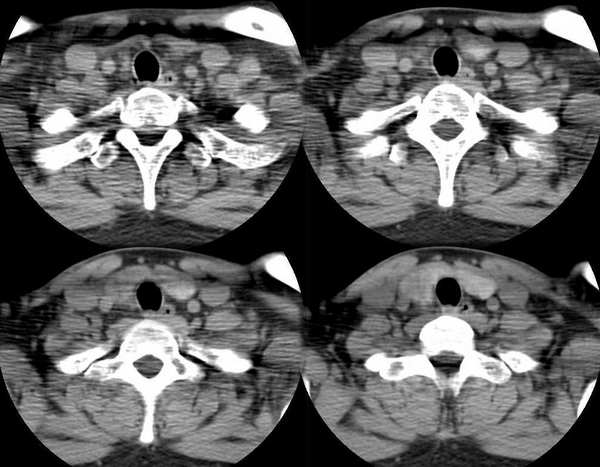

男,25岁,体温39.3度,发现右侧颈部包块.

右侧甲状腺内边界不甚清楚之占位,增强后呈轻度强化。

1.考滤炎性病变可能性大;2.不除外ca。

平扫和增强病灶境界欠清、形状不规则,考虑甲状腺癌可能。

此病例特点:1、年轻男性,基本上是高热;2、右侧甲状腺肿大呈边界不清之低密度,但甲状腺境界清晰;3、基本没有增强但低密度的周边略呈边缘增强反应;4、最好补充病史:痛否?时间?(如痛、急性起病。)

据此,以甲状腺急性炎症可能性大。